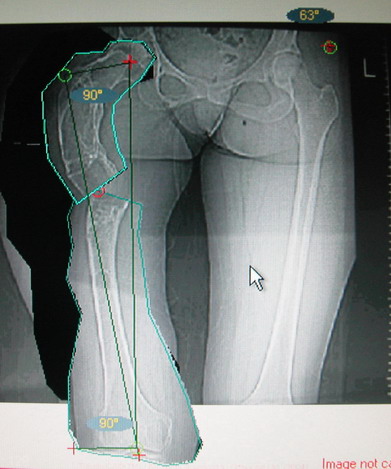

На мой взгляд, для того, чтобы правильно исправить данную деформацию, необходимо обследование больного, которое должно включить в себя, помимо осмотра: 1. Рентгенограммы ( передне-задние и боковые)нижних конечностей на всю длину стоя . 2. Компьютерная томография для измерения длины нижних конечностей. 3. Комьютерная томография тазобедоенных, коленных и голеностопных суставов для измерения углов антеверсии тазобедренных суставов и ротации голеней. Это тот минимум, который должен входить в предоперационное обследование каждого больного с тяжёлыми формами деформаций конечностей.

Поскольку в данном случае имеется дело с довольно большой деформацией с укорочением, одномоментная её устранение с внутренней фиксацией, чревато с одной стороны неправильной коррекцией, с другой, нейроваскулярными осложнениями.

Моё мнение, что двойная остеотомия бедра с аппаратом Илизарова + Гексаподный механизм, или Тэйлора, В данной ситуации является методом выбора. Я очень извеняюсь за качество прилагаемых снимков, в которых я постарался отразить разницу междe одной и двумя остеотомиями бедра.